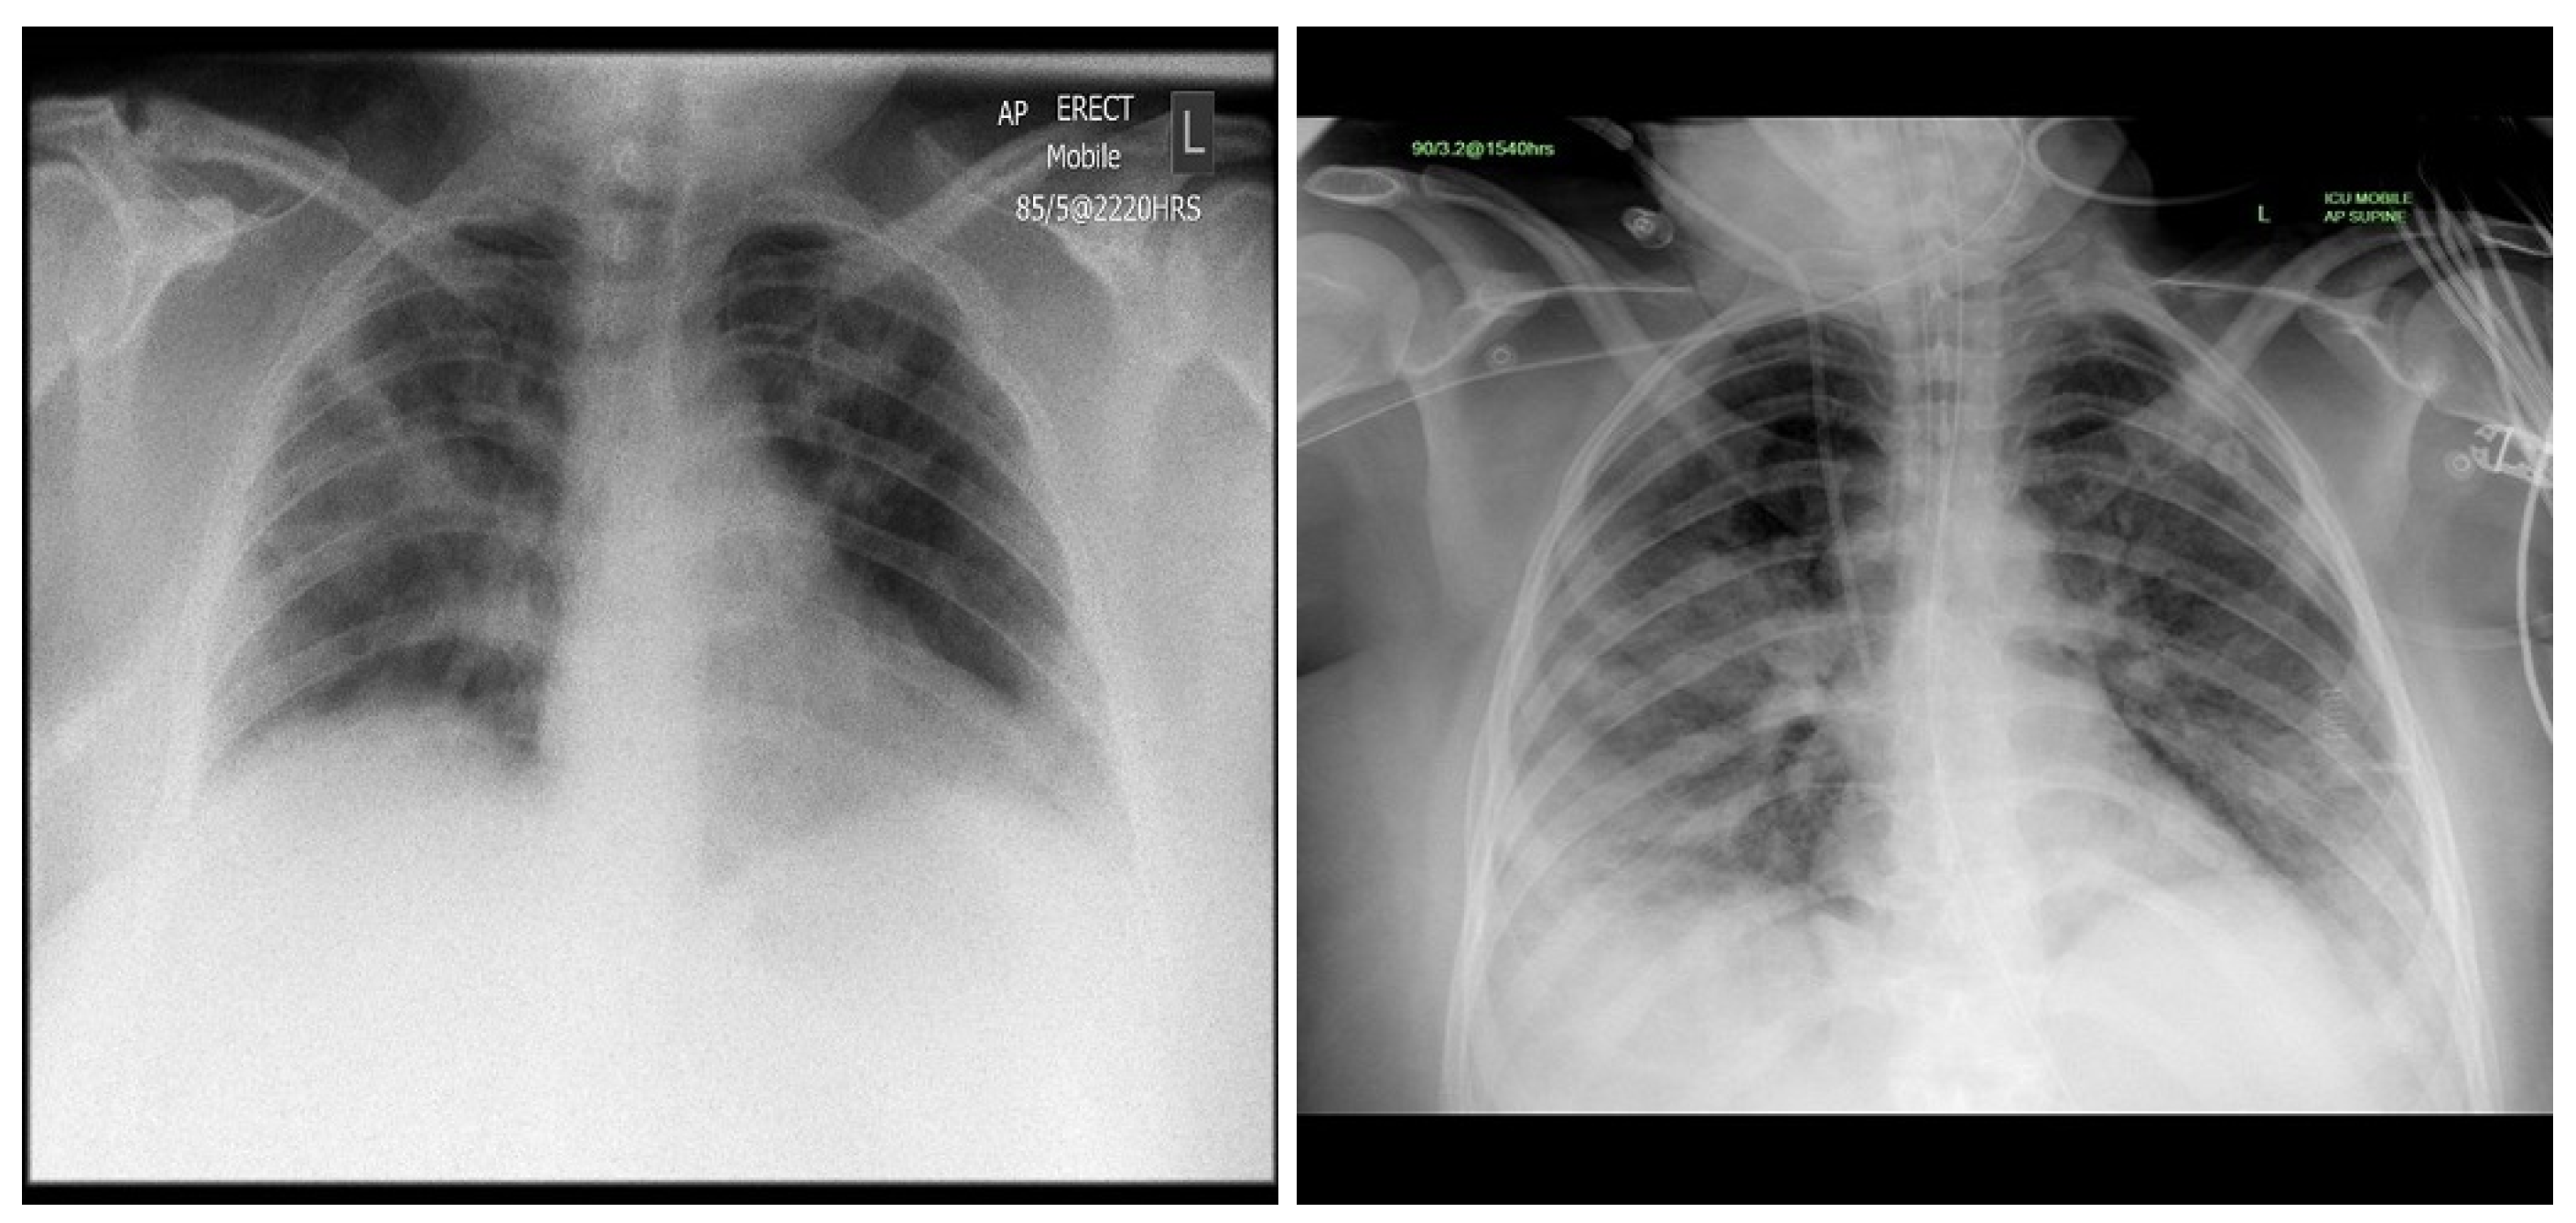

3.1. COVID-19 Image Data Collection (CIDC)

3.2. COVID-19 Radiography

3.3. BIMCV COVID19+

3.4. RSNA